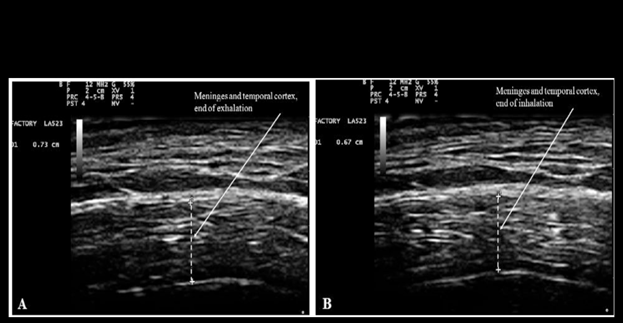

Figure 11, reproduced below from Ruggiero et al.,31 shows the changes of thickness and water content of brain cortex and meninges with inspiration and exhalation

Figure 11 Measurement of combined thickness of the meninges and the cortex of the temporal lobe at the end of forced voluntary exhalation (A: 7.3 mm), and inhalation (B: 6.7 mm). Reproduced from Figure 5 of Ruggiero et al.46 under the terms and conditions of the Creative Commons Attribution 4.0 International Public License (CC-BY-4.0) license https://creativecommons.org/licenses/by/4.0/.